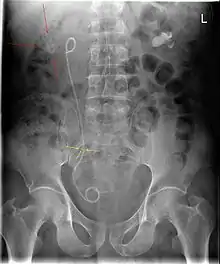

الدعامة الحالبية أو الاستنت الحالبي[1] (بالإنجليزية: Ureteric stent)، عبارة عن أنبوب رفيع يتم إدخاله في الحالب لمنع أو معالجة انسداد تدفق البول من الكلى. يتراوح طول الدعامات المستخدمة في المرضى البالغين بين 24 و 30 سم. بالإضافة إلى ذلك، تأتي الدعامات بأقطار أو مقاسات مختلفة، لتناسب أحجام الحالب المختلفة. وعادةً ما يتم إدخال الدعامة بواسطة منظار المثانة. قد يتم لف أحد طرفي الدعامة أو كليهما لمنعه من التحرك خارج الحالب؛ وهذا ما يُسمى بـ دعامة JJ، دعامة J المزدوجة أو دعامة ذيل خنزير.